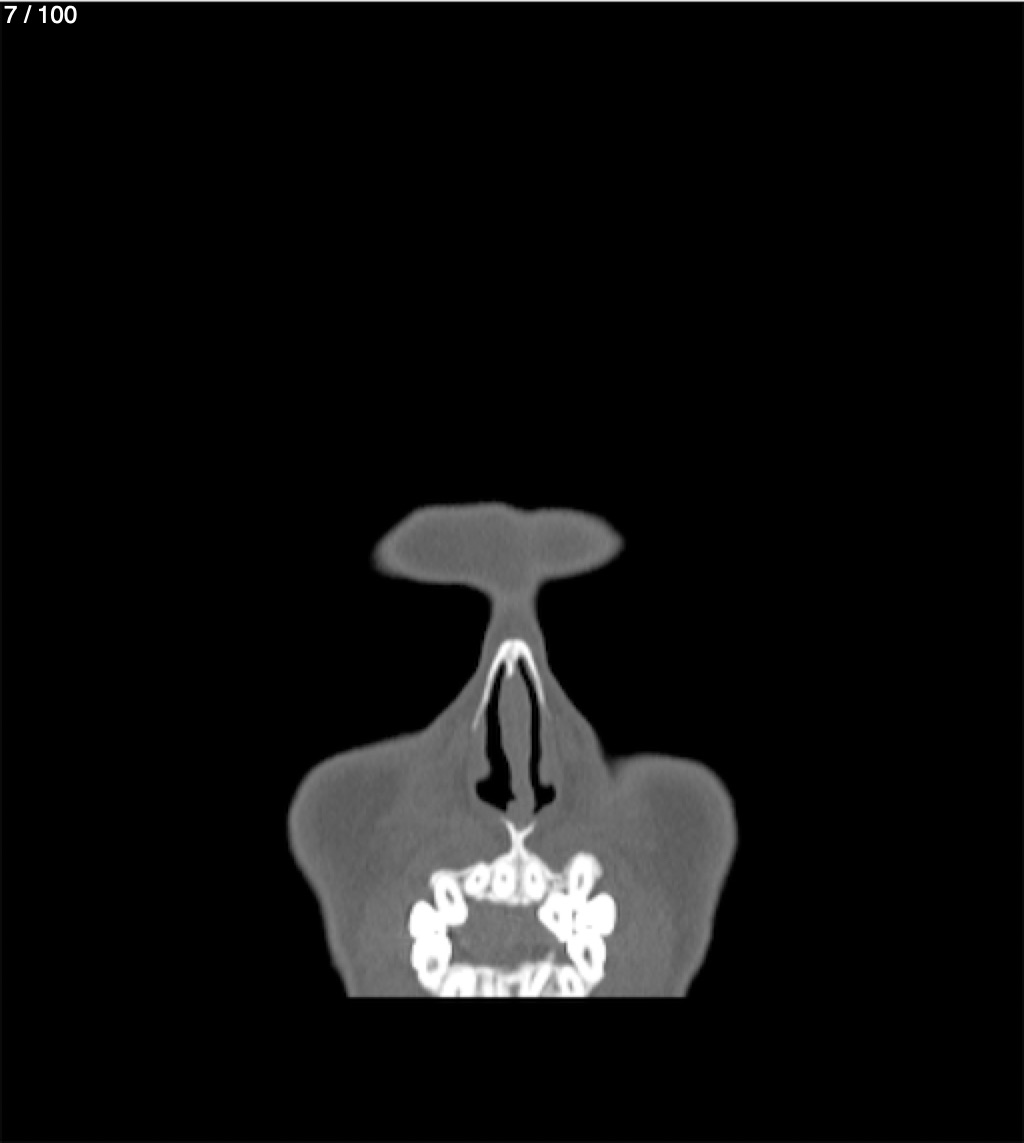

Yonelly Barrios Diaz 35A - T.C Craneo